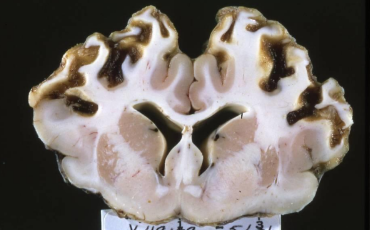

What is this in a cow? Diagnostic test.

Cerebrocortical necrosis

Autofluorescence under UV light